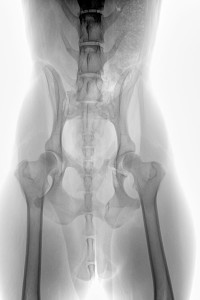

Die Spinone ltaliano Hündin „Ajenna“ gerufen Jenna, geb. April 2013, wk, ist am 06. Oktober 2015 auf der unweit entfernten Bundesstraße vor ein Auto gelaufen und wurde angefahren. Durch den seitlichen Aufprall auf die linke Körperseite kam es zu einem stumpfen Trauma im Brustbereich mit Lungenrissen und das Becken wurde mehrfach frakturiert. Wie auf den RÖ-Bildern zu sehen, war das Schambein verschoben, das Becken gebrochen, aber die größte Sorge machte uns die Fraktur im caudalen Bereich des Acetabulums. Da der Hund das Hinterbein mäßig belasten konnte und die Band- und Kapselstrukturen des Hüftgelenkes scheinbar intakt und nicht gerissen waren (der Femurkopf war nicht luxiert), sah der hinzugezogene Orthopäde von einer sofortigen OP ab und wollte zunächst den Heilungsverlauf beobachten.

Auf der Kontroll-RÖ-Aufnahme vom 19. Okt. konnte noch keine Kallusbildung festgestellt werden.